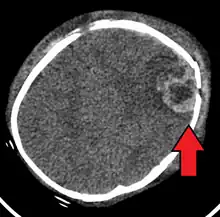

An intraparenchymal bleed with overlying skull fracture from shaken baby syndrome

Diagnostic methodCT scan[1]

Diagnosis can be difficult as symptoms may be nonspecific.[1] A CT scan of the head is typically recommended if a concern is present.[1] It is unclear how useful subdural haematoma, retinal hemorrhages, and encephalopathy are alone at making the diagnosis.[25]